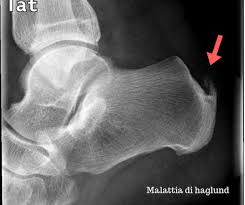

Haglund Deformity Radiology : Haglund Deformity Radiology Case Radiopaedia Org - Haglund's deformity is named after patrick haglund, who defined the condition in 1927.. This condition is often precipitated by wearing shoes with rigid backs that rub against the heel. Does haglund's deformity go away? Haglund deformity, also known as a pump bump , bauer bump, or mulholland deformity, is defined as bony enlargement formed at the posterosuperior aspect of the calcaneum. Haglund's deformity is characterized as an enlarged prominence of the superior aspect of the posterior calcaneus, which can cause painful inflammation within the retrocalcaneal bursa and anterior surface of the achilles tendon as a result of mechanical irritation. Insertional achilles tendinopathy retrocalcaneal bursitis haglund deformity (i.e.

Haglund deformity, also known as a pump bump , bauer bump, or mulholland deformity, is defined as bony enlargement formed at the posterosuperior aspect of the calcaneum.

Correct shoes that are supportive may prevent it. As associated problems such as heel bursitis settle, the size of the lump should reduce, but the bony why is it called haglunds deformity? Radiographic evaluation of haglund's deformity. The authors describe a new method of radiologic measurement of haglund's deformity, based on a radiologic study of 31 feet operated for posterior heel pain and more especially for calcaneal tendinopathies related to deformity of the calcaneus, and on a series of 60 asymptomatic feet. This deformity leads to retrocalcaneal bursitis. Haglund deformity, also known as a pump bump, bauer bump, or mulholland deformity, is defined as bony enlargement formed at the posterosuperior aspect of the calcaneum. Haglund's deformity is a bony enlargement at the level of the posterior part of the heel. The primary symptom of haglund's deformity is pain at the back of the heel. Haglund's deformity is named after patrick haglund, who defined the condition in 1927. There is a noticeable swelling on the back of heel also called bump. This includes home remedies and. Haglund's deformity is a bony enlargement on the back of the heel. Haglund's syndrome is a group of signs and symptoms consisting of haglund's deformity (which is an exostosis of the posterior calcaneal tuberosity) in combination with retrocalcaneal bursitis.

It refers to the mechanical irritation between the posterior section of the calcaneus (heel bone) and the achilles tendon. It thus proves markedly superior to previously described radiologic formulations, since it allows not only for the size and site of the deformity of the @article{chauveaux2005anr, title={a new radiologic measurement for the diagnosis of haglund's deformity}, author={d. It affects the bone and the soft tissues. It is a small, often pointy haglund's deformity can cause pain at the back of the heel increasing during strain. Haglund deformity radiology reference article. Haglund's deformity is where bone grows on the heel bone (calcaneus). Halgund's deformity is a condition in which a bony enlargement is formed in the heel. Insertional achilles tendinopathy retrocalcaneal bursitis haglund deformity (i.e.

The presence of a haglund's deformity narrows this space considerbly thereby casuing or exacerbating problems such as retrocalcaneal bursitis. When this bony enlargement rubs against the achilles tendon and overlying bursa, inflammation of the retrocalcaneal bursa occurs. Does haglund's deformity go away? Haglund's deformity, also called pump bump, winter heel, mulholland deformity, or retrocalcaneal exostosis, is a bony enlargement of the posterosuperior heel bone, called the calcaneus, at the insertion site of the haglund syndrome: The soft tissue near the achilles tendon becomes irritated when the bony enlargement rubs against shoes.